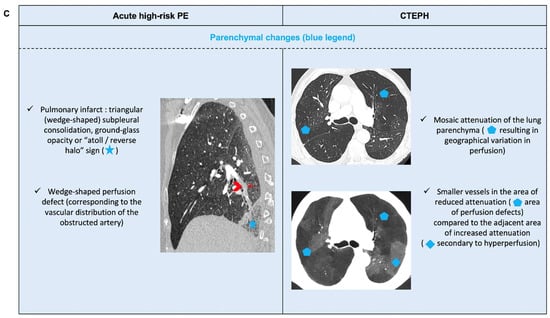

6.2. Acute PE with Underlying Chronic Thrombo-Embolic Pulmonary Hypertension